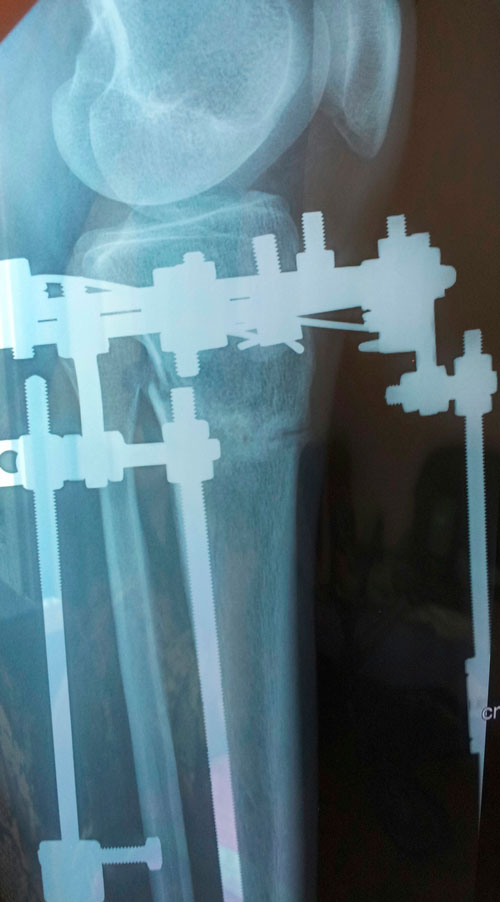

Рентген в 59 дней

Напоминаю:рентгеновские снимки делать на одной плёнке (вначале прямая проекция, затем боковая проекция), чтобы видеть ось.

Когда фотографируете R- снимки, не закрывайте опознавательные буквы (где левая, а где правая голень?)